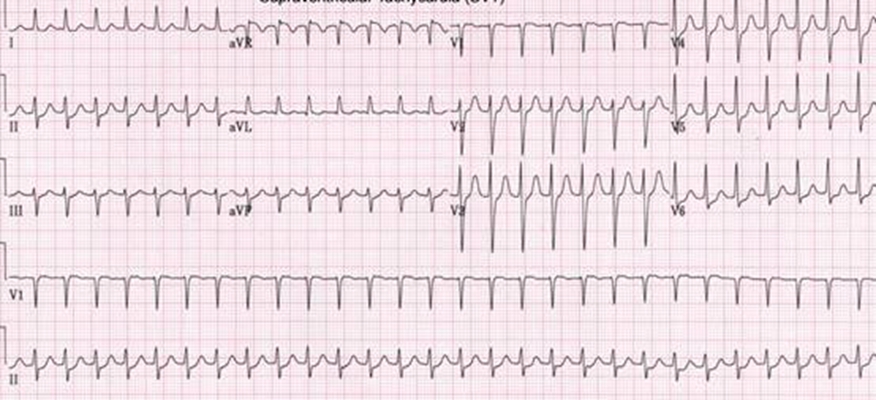

預激綜合徵心電圖 (9)

預激綜合徵心電圖 (90)

預激綜合徵心電圖 (91)

預激綜合徵心電圖 (92)

預激綜合徵心電圖 (93)

預激綜合徵心電圖 (94)

預激綜合徵心電圖 (95)

預激綜合徵心電圖 (96)

A:預激綜合徵典型的心電圖表現是竇性心搏的PR間期縮短,短於0.12s,而且導聯的QRS波群時間超過0.12s。QRS波群起始部分會有粗鈍,終末部分正常,甚至會導致ST-T波型呈現繼發性的改變,甚至於QRS波群主波方向相反。預激綜合徵是指心房……

A:預激綜合徵是很少見的心律失常,是房室傳導異常的一種類型,提早興奮心室的一部分或全部,引起心室肌提前激動,常合併室上性心動過速。心電圖可見PR間期縮短小於0.12秒;QRS時限延長0.11秒以上;QRS波群起始部粗鈍,繼發性ST-T改變。沒有……

A:預激綜合徵的定義是:因為心房和心室之間存在著異常傳導通路,使部分電活動從心房經過這個通路傳導到心室,引起心室局部心肌細胞發生提前除極,在心電圖上可以出現預激波,這就是預激綜合徵。有預激綜合徵的患者會因這條特殊通路的存在,導致電活動在心房心室……

A:預激綜合徵合併房速的時候,心電圖可以出現快速而且寬大畸形的QRS波群,有點類似於室性心動過速,典型的預激波有可能會被覆蓋。合併房速的時候會有極快速的心室率、QRS波群會寬大畸形,也有可能比較易變和複雜。患有預激綜合症合併房速,如果有明顯的心……